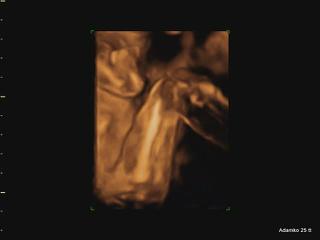

@adikad už som pozerala tvoje fotky v albume, je naozaj krásny 🙂 a ako jasne a zreteľne je vidno tváričku!